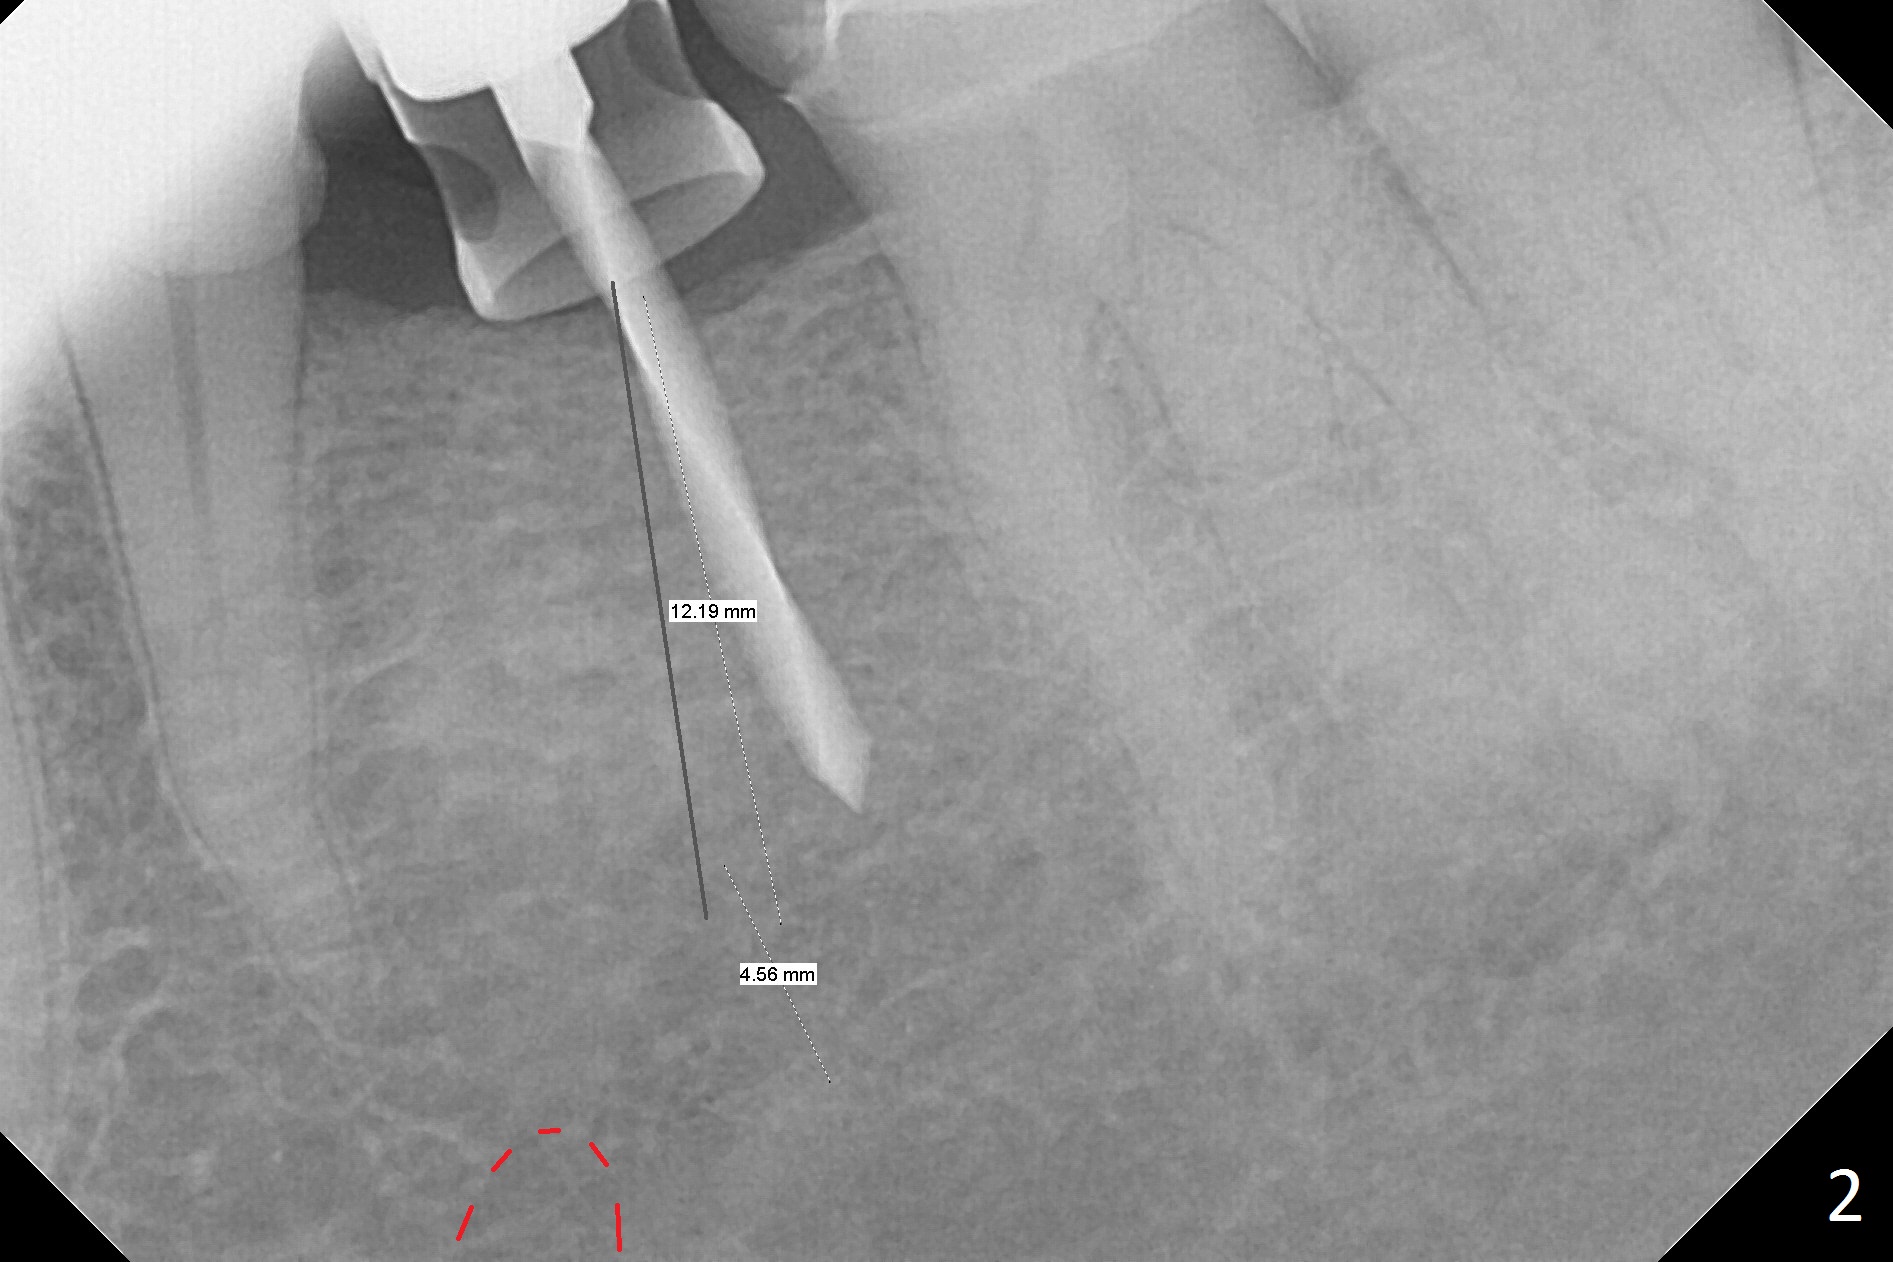

Initial osteotomy with 1.6 mm drill for 11 mm seems to be distal (Fig.1). The trajectory should be changed as shown by the black line in Fig.2; the drawback would be close to the Mental Loop (red line). Fortunately the trajectory is changed, but not so much as to be close the Loop when a 4x11 mm dummy implant is placed (Fig.3). When a 4x13 mm IBS is placed with 46 Ncm, there is clearance from the Loop (Fig.4-6). In fact there is no postop paresthesia. The main point is no block anesthesia. Infiltration anesthesia is administered with 34 mg Xylocaine with 17 mcg Epinephrine. The patient experiences dull pain when the implant is placed (Fig.4-6). After further anesthesia with 68 mg Septocaine, 17 mcg Epinephrine, the implant is torqued for a few turns (still with some discomfort). Finally autogenous bone with Osteogen is placed around the implant following placement of a 4.5x4(2) mm abutment. To reduce anxiety, a shorter implant should have been used. The patient complains of cold sensitivity in the lower left quadrant 4 months postop (Fig.7): the implant apparently close to the Mental Loop. Without an immediate provisional, the gingiva around the abutment is healthy.